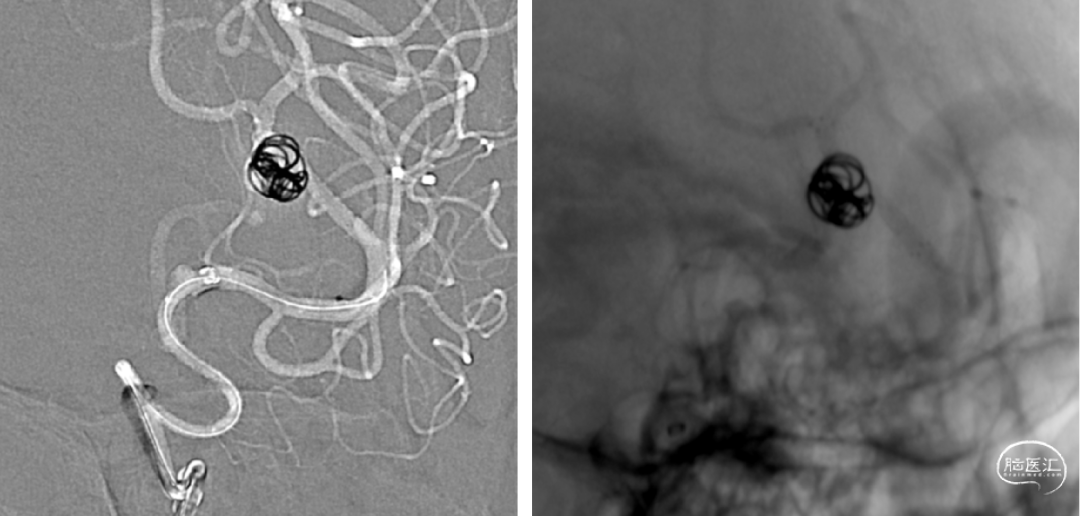

手术规划:FD+弹簧圈

FRED 3.0x14/19

术后CT